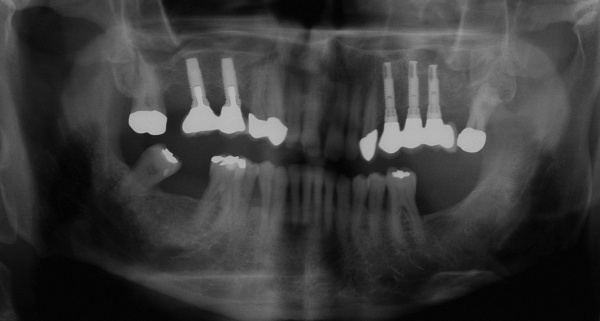

Der Erstbefund vom 20.08.1998 zeigte eine lokalisiert entzündliche marginale Gingiva mit Blutungsneigung auf Sondierung (SBI 32 %) vorrangig in regio 17, 11, 21, 24, 27, 36, 37, 41, 46. Austritt von Pus aus der Tasche an 22. Die Sondiertiefen waren durchweg erhöht, an einzelnen Parodontien konnten bis zu 12 mm sondiert werden (s. Abb. 12). Generalisiert weiche Beläge (API 46 %), harte Beläge in der UK-Front. An 41 singuläre parodontale Rezession und Zahnlockerung des Grades II, hier auch sehr schmale keratinisierte Gingiva. Mobilitätstest und Blanchingtest positiv. Der Röntgenbefund der Panoramaschichtaufnahme vom 11.08.1999 (s. Abb. 13) zeigt einen generalisierten horizontalen Knochenabbau mit vertikalen Einbrüchen in regio 17, 24, 25, 26, 36, 41 und 47. Wurzelfüllung an 36. Konkremente sichtbar. 18 elongiert. 38 und 48 halbretiniert mit Aufhellung distal.

Mit der Transplantation eines freien Schleimhauttransplantats im Januar 2001 konnte die aktive parodontologische Therapie abgeschlossen werden, der Patient wurde zur Unterstützenden Parodontitistherapie in das Recallsystem der FU VIIa aufgenommen. Der Patient stellte sich dabei halbjährlich zur Durchführung von professionellen Zahnreinigungen vor, die durch die bereits beschriebenen Elemente der Erhaltungstherapie ergänzt wurden. Ein wichtiges Element der Erhaltungstherapie ist die regelmäßige parodontale Diagnostik mit der Erstellung eines Parodontalstatus, um gegebenenfalls Rezidive frühzeitig erkennen und behandeln zu können. Im Jahre 2006 kam es an einzelnen Zähnen zu Rezidiven, es konnten Sondiertiefen von bis zu 7mm sondiert werden. Es wurde daher ein Scaling/Rootplaning der rezidivierenden Taschen durchgeführt, an einzelnen Zähnen erfolgten im Jahre 2008 zudem weiterführende parodontalchirurgische Maßnahmen im Sinne von Lappenoperationen (s. Abb. 16). Im Rahmen der unterstützenden Parodontitistherapie erfolgte neben den schon erwähnten halbjährlichen professionellen Zahnreinigungen im November 2012 eine erneute subgingivale Instrumentierung an 21, 24, 28, 41, 46. Die letzte Vorstellung des Patienten erfolgte im April 2015 (s. Abb. 17, 18, 19). Dabei stellte sich die marginale Gingiva entzündungsfrei dar, die approximalen Sondiertiefen betrugen durchschnittlich zwei bis drei Millimeter, geringgradig erhöhte Sondiertiefen verbleiben an 21, 28, 36, 47. Die häusliche Mundhygiene des Patienten stellte sich wie schon über den gesamten Beobachtungszeitraum mit einem API von 30 % als gut dar. Die periimplantären Gewebe zeigten sich bei der Vorstellung im April 2015 unauffällig.